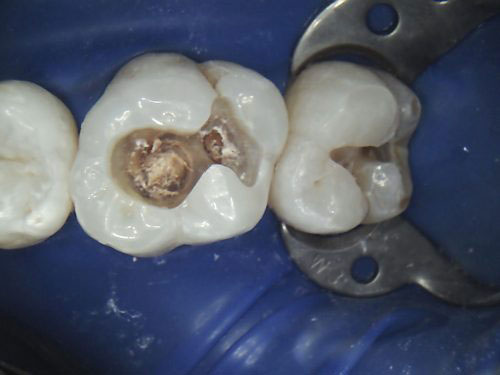

钻掉腐烂的龋坏及以前的修复材料

使用通常称为牙钻的高速手机,牙医将去除腐烂和受损的牙齿结构。如果是继发性的龋坏,牙医将删除任何以前的牙科修复体。他们还将去除任何腐烂和无支撑的牙齿部分。必须清洁牙齿腔,只留下合理的牙齿结构。在此过程中,牙科护士将使用另一种工具吸出水分和碎屑。